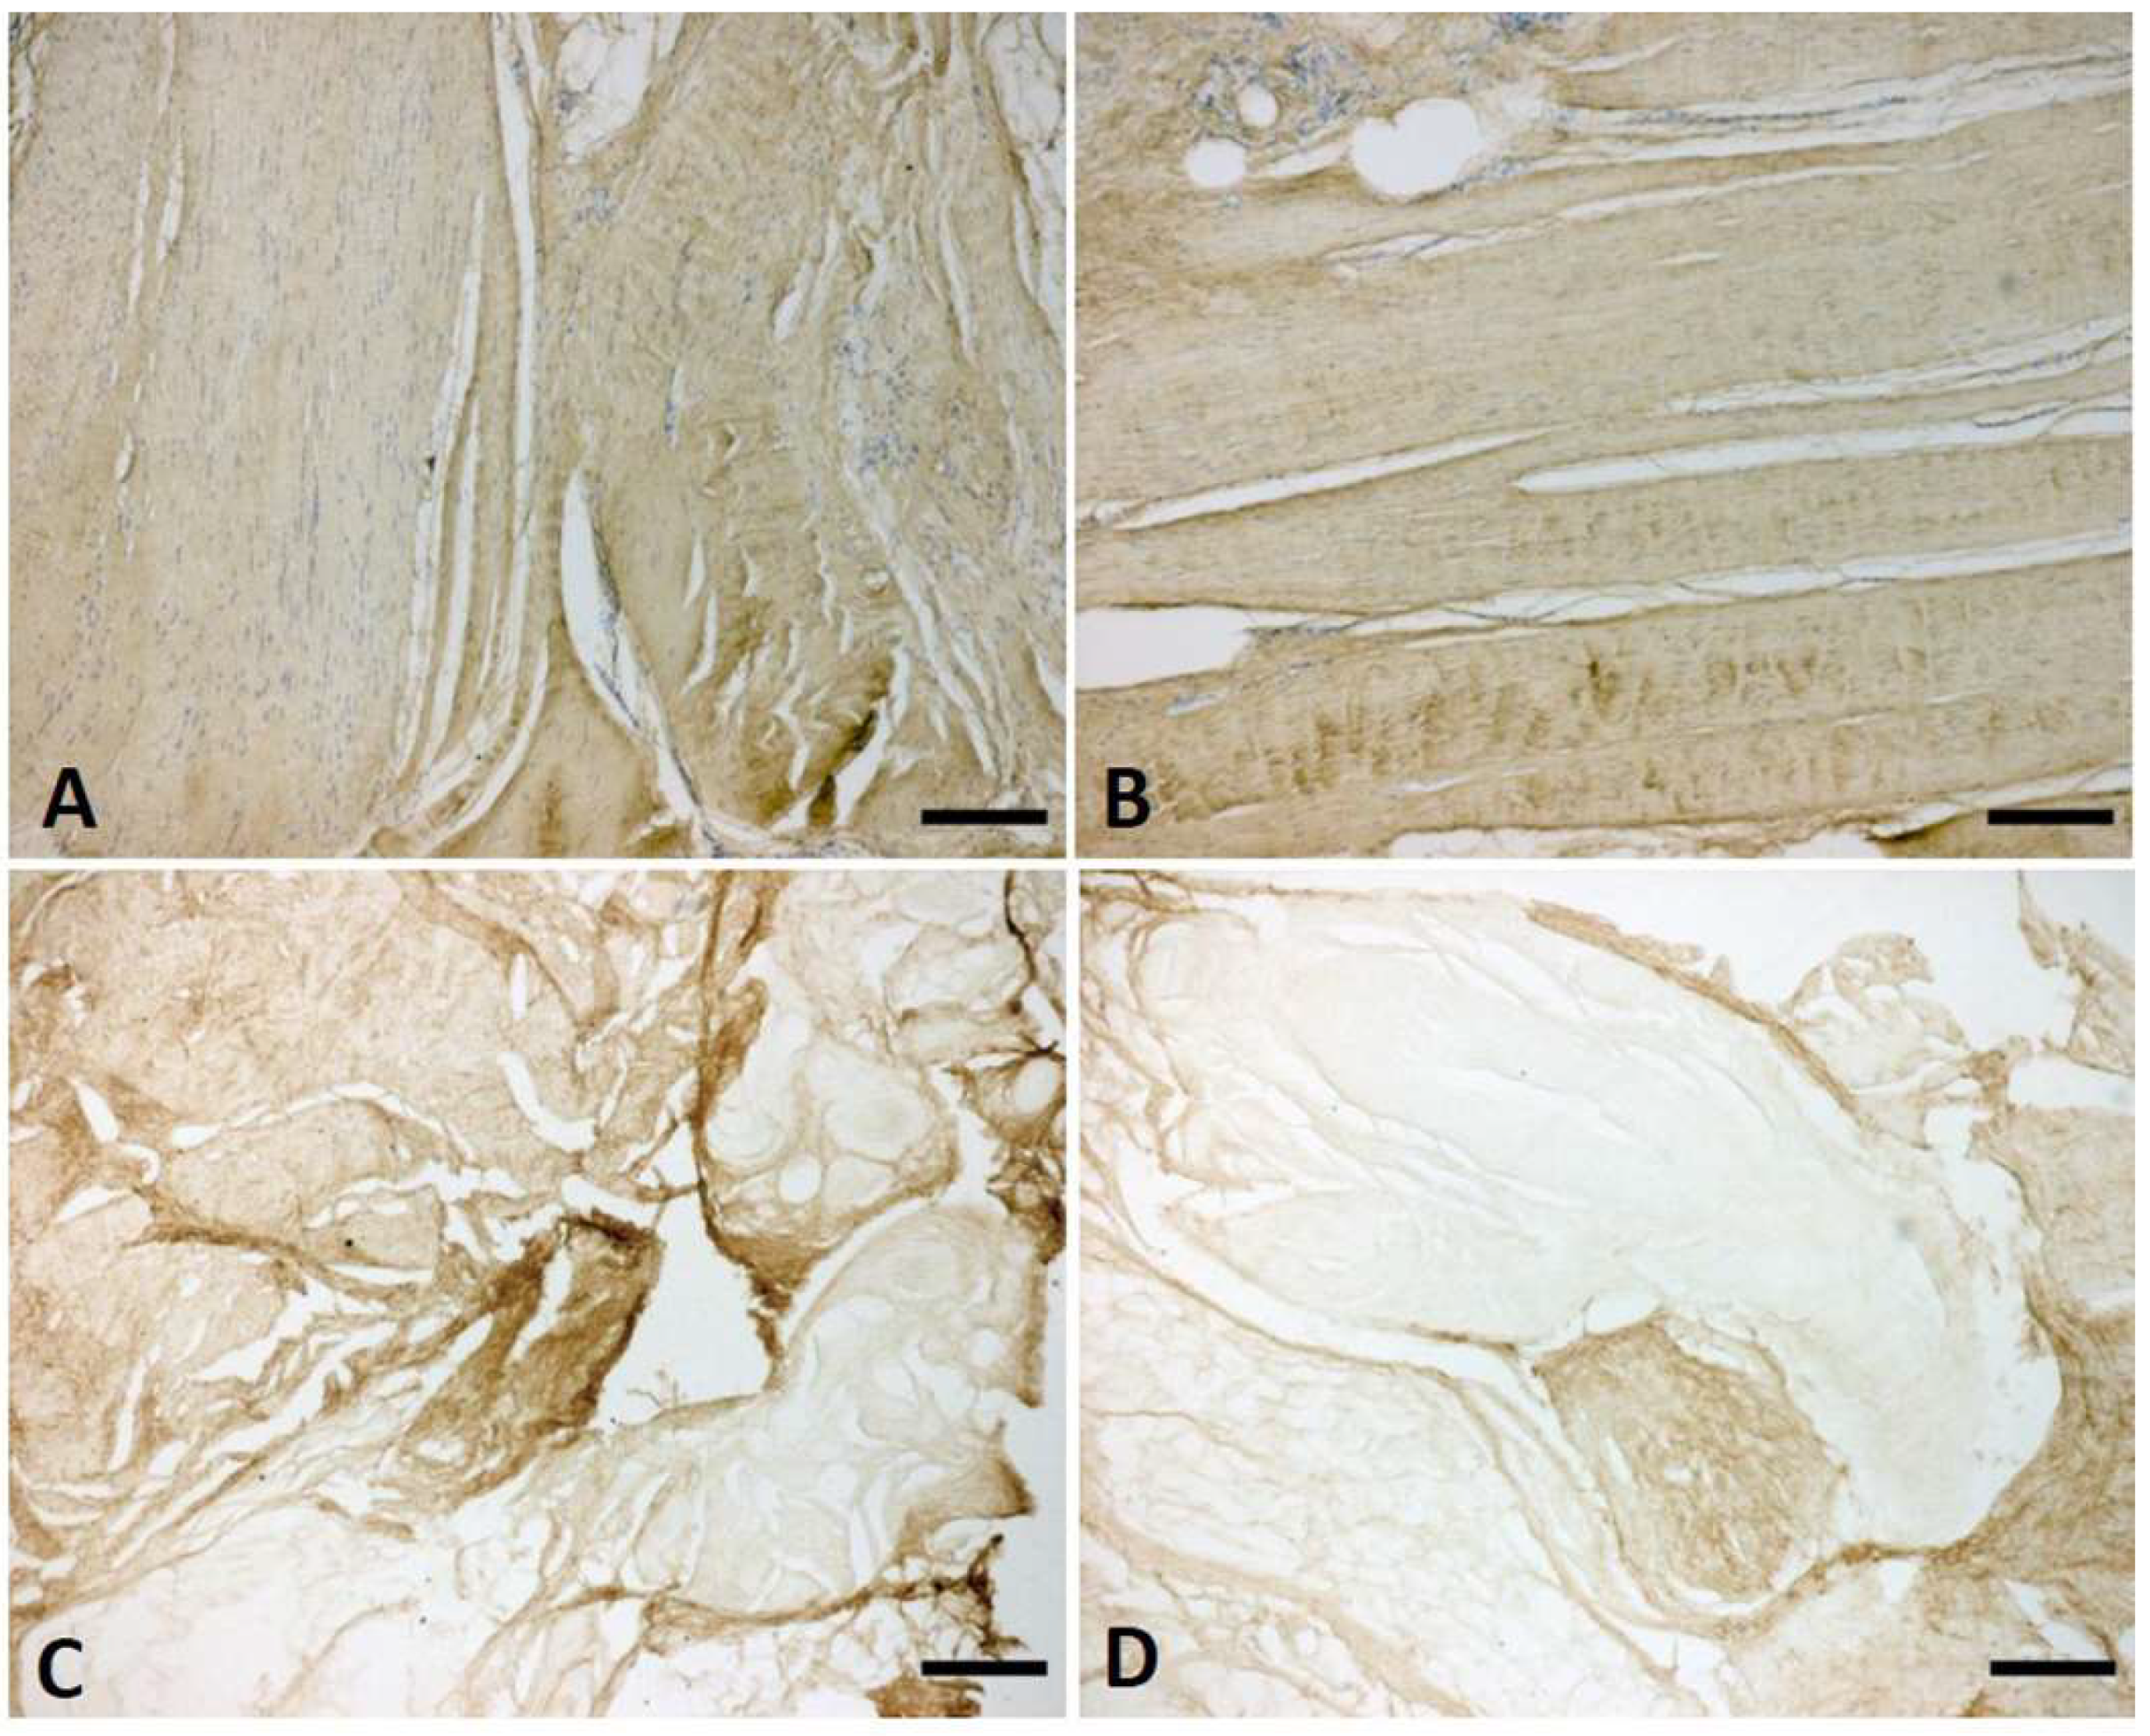

The immunostaining with anti-Collagen-I and III showed a homogeneous distribution and arrangement of the collagen fibres in both the longitudinal and vertical fibres (Figure 7). The collagen assay kit and the immunoblotting permitted a quantification of the collagen in the vertical and longitudinal septa at various stages of Dupuytren’s disease.

Figure 7. Anti-Collagen-I (A,B) and anti-Collagen-III (C,D) in vertical (AC) and longitudinal (BD) fibres of palmar aponeurosis at stage 2 of Dupuytren’s disease. Scale bars: 200 µm.